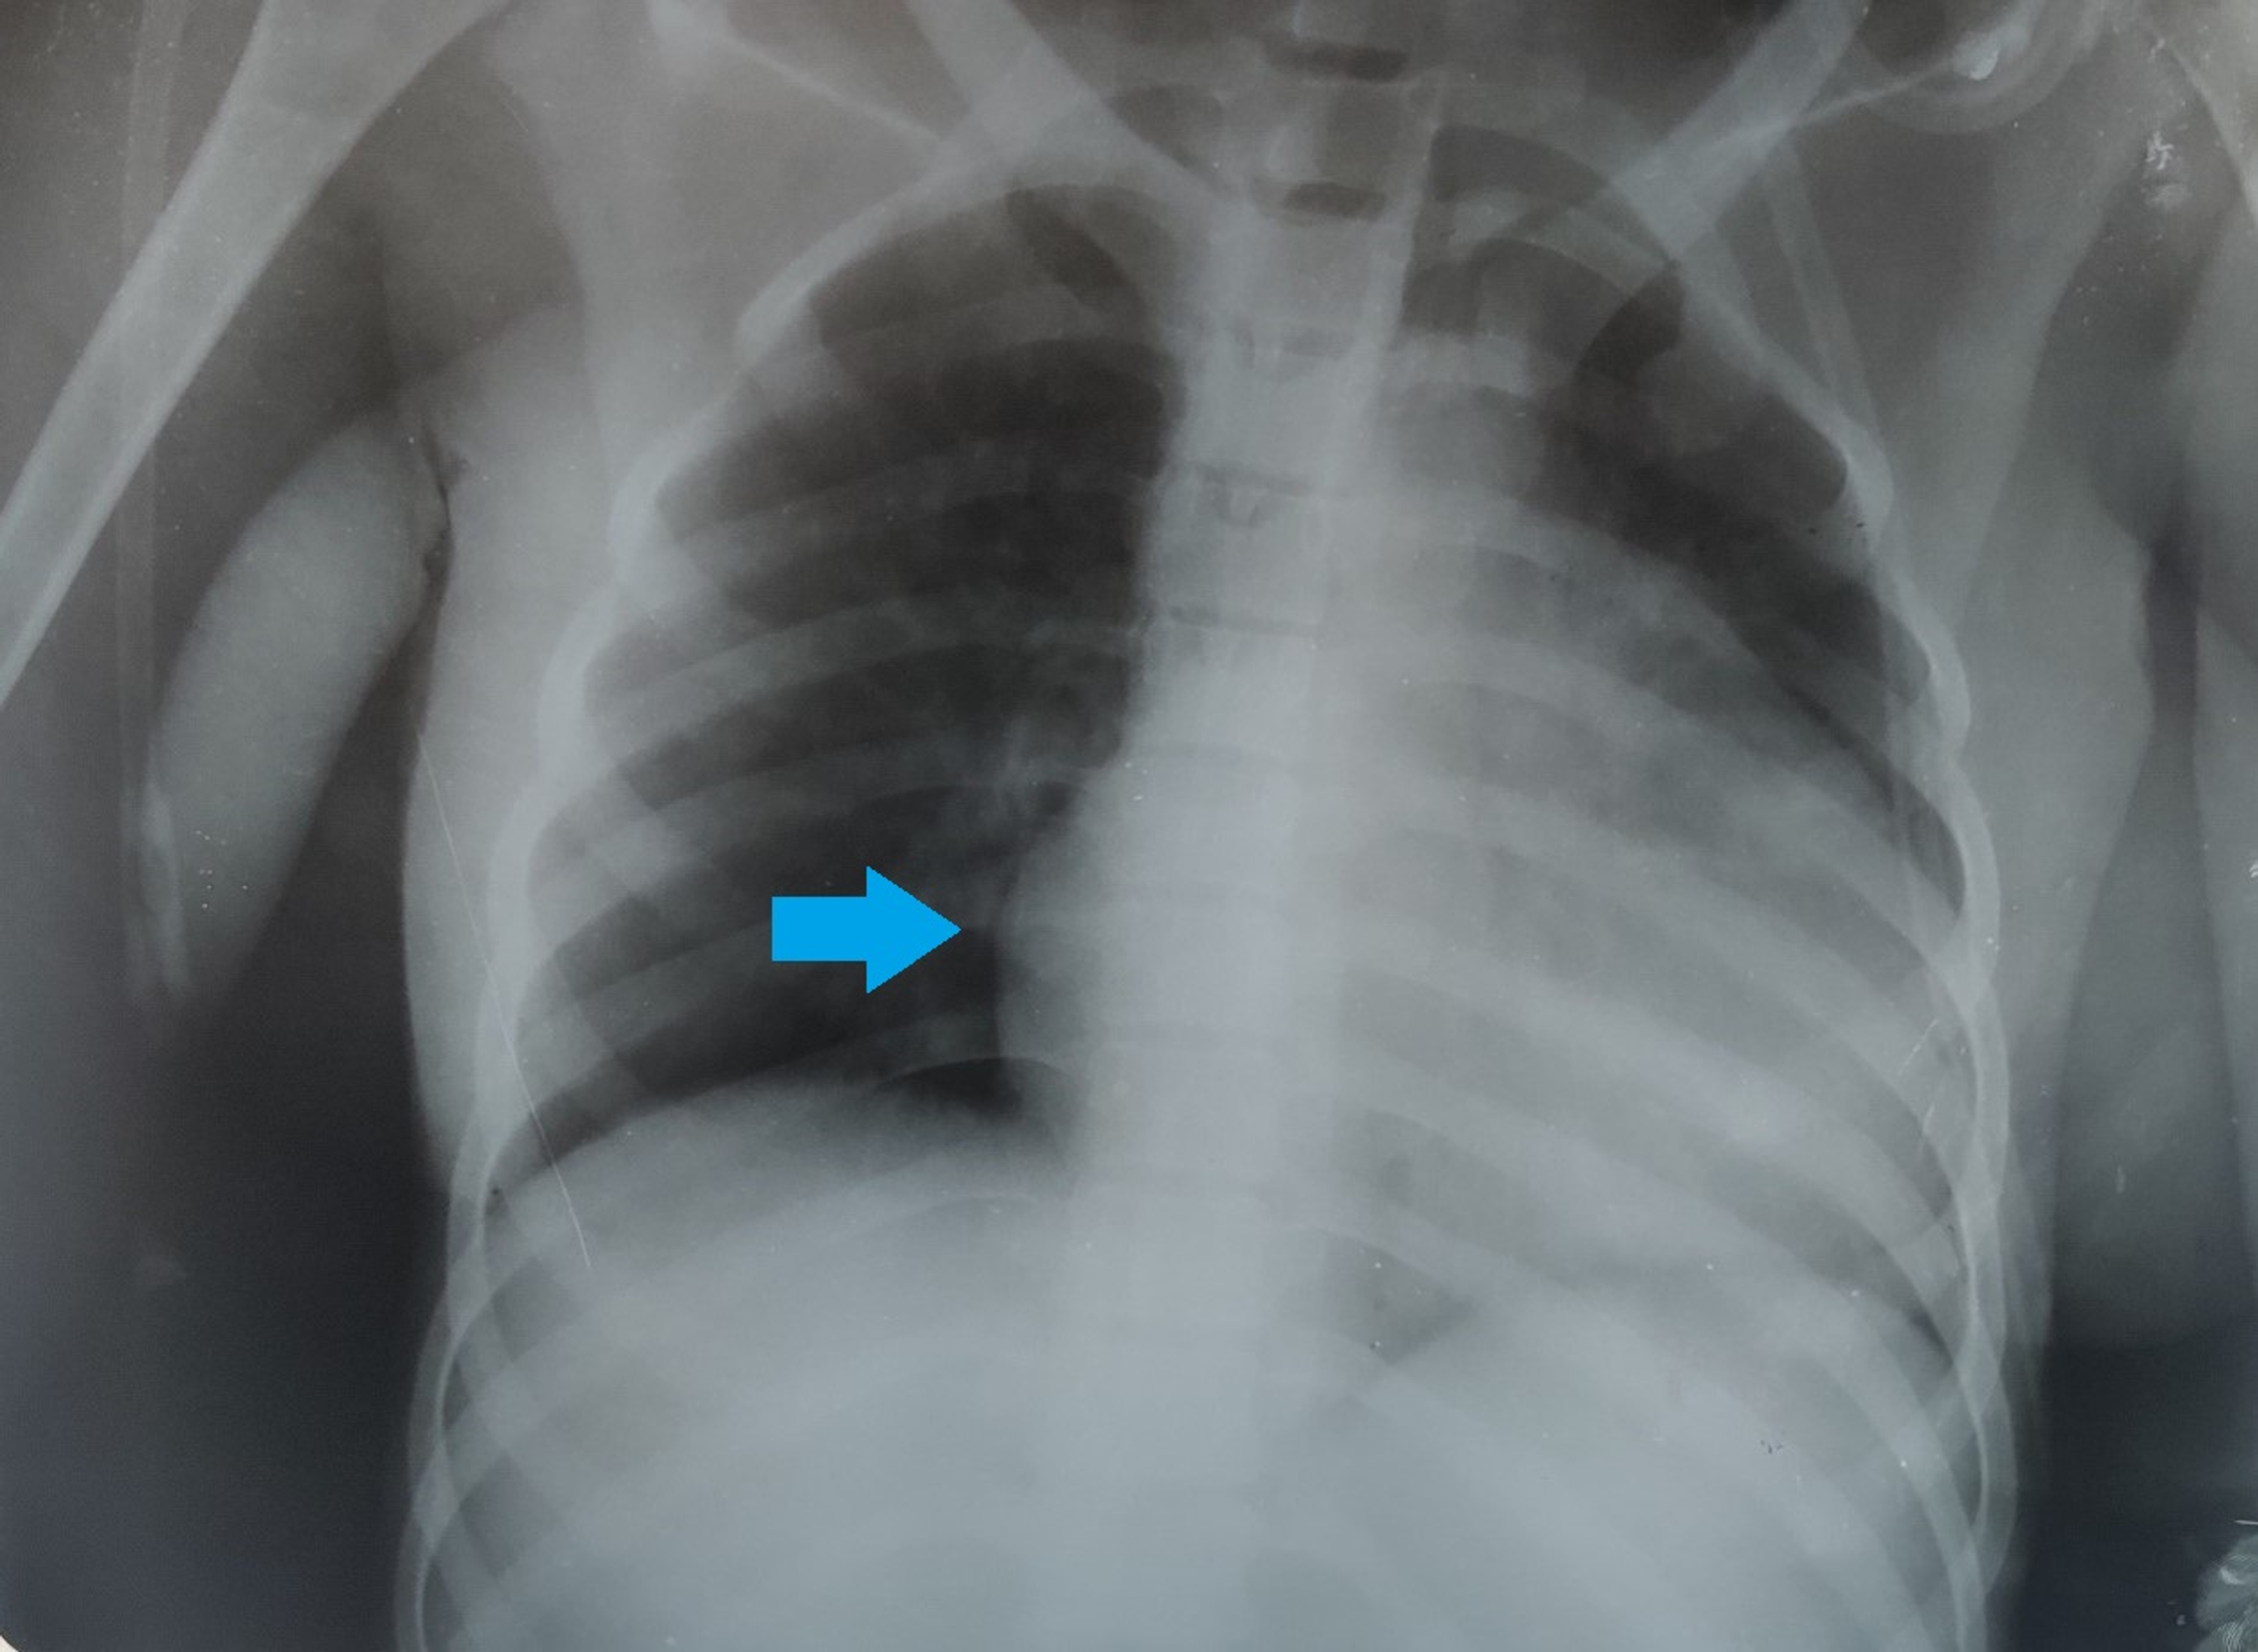

Chest X-Ray Findings In Lupus . As an example, the diagnosis of sle is more likely to be present in a young woman who develops fatigue, arthralgia, and pleuritic chest. In patients showing lung complications, 72% displayed symptoms, which most frequently consisted of pleuritic chest. Systemic lupus erythematosus (sle) is an unusually complex autoimmune disease that is encountered in every radiology subspecialty. Thoracic manifestations of systemic lupus erythematosus. Pleural involvement is common in sle, occurring in up to 93 percent in autopsy series, and can be manifest as pleuritic chest. Please refer to the main article on. Thoracic manifestations of systemic lupus erythematosus (sle) can be variable. On ed presentation the patient’s vital signs showed tachycardia (hr 120s), tachypnea (rr 28), blood pressure (110/60), and an oxygen saturation of 96% on 2l nasal cannula.

Atelectasis (Right Lower Lobe) Explanation of Chest Xray Findings Chest X-Ray Findings In Lupus On ed presentation the patient’s vital signs showed tachycardia (hr 120s), tachypnea (rr 28), blood pressure (110/60), and an oxygen saturation of 96% on 2l nasal cannula. In patients showing lung complications, 72% displayed symptoms, which most frequently consisted of pleuritic chest. Thoracic manifestations of systemic lupus erythematosus. Thoracic manifestations of systemic lupus erythematosus (sle) can be variable. Please refer. Chest X-Ray Findings In Lupus.